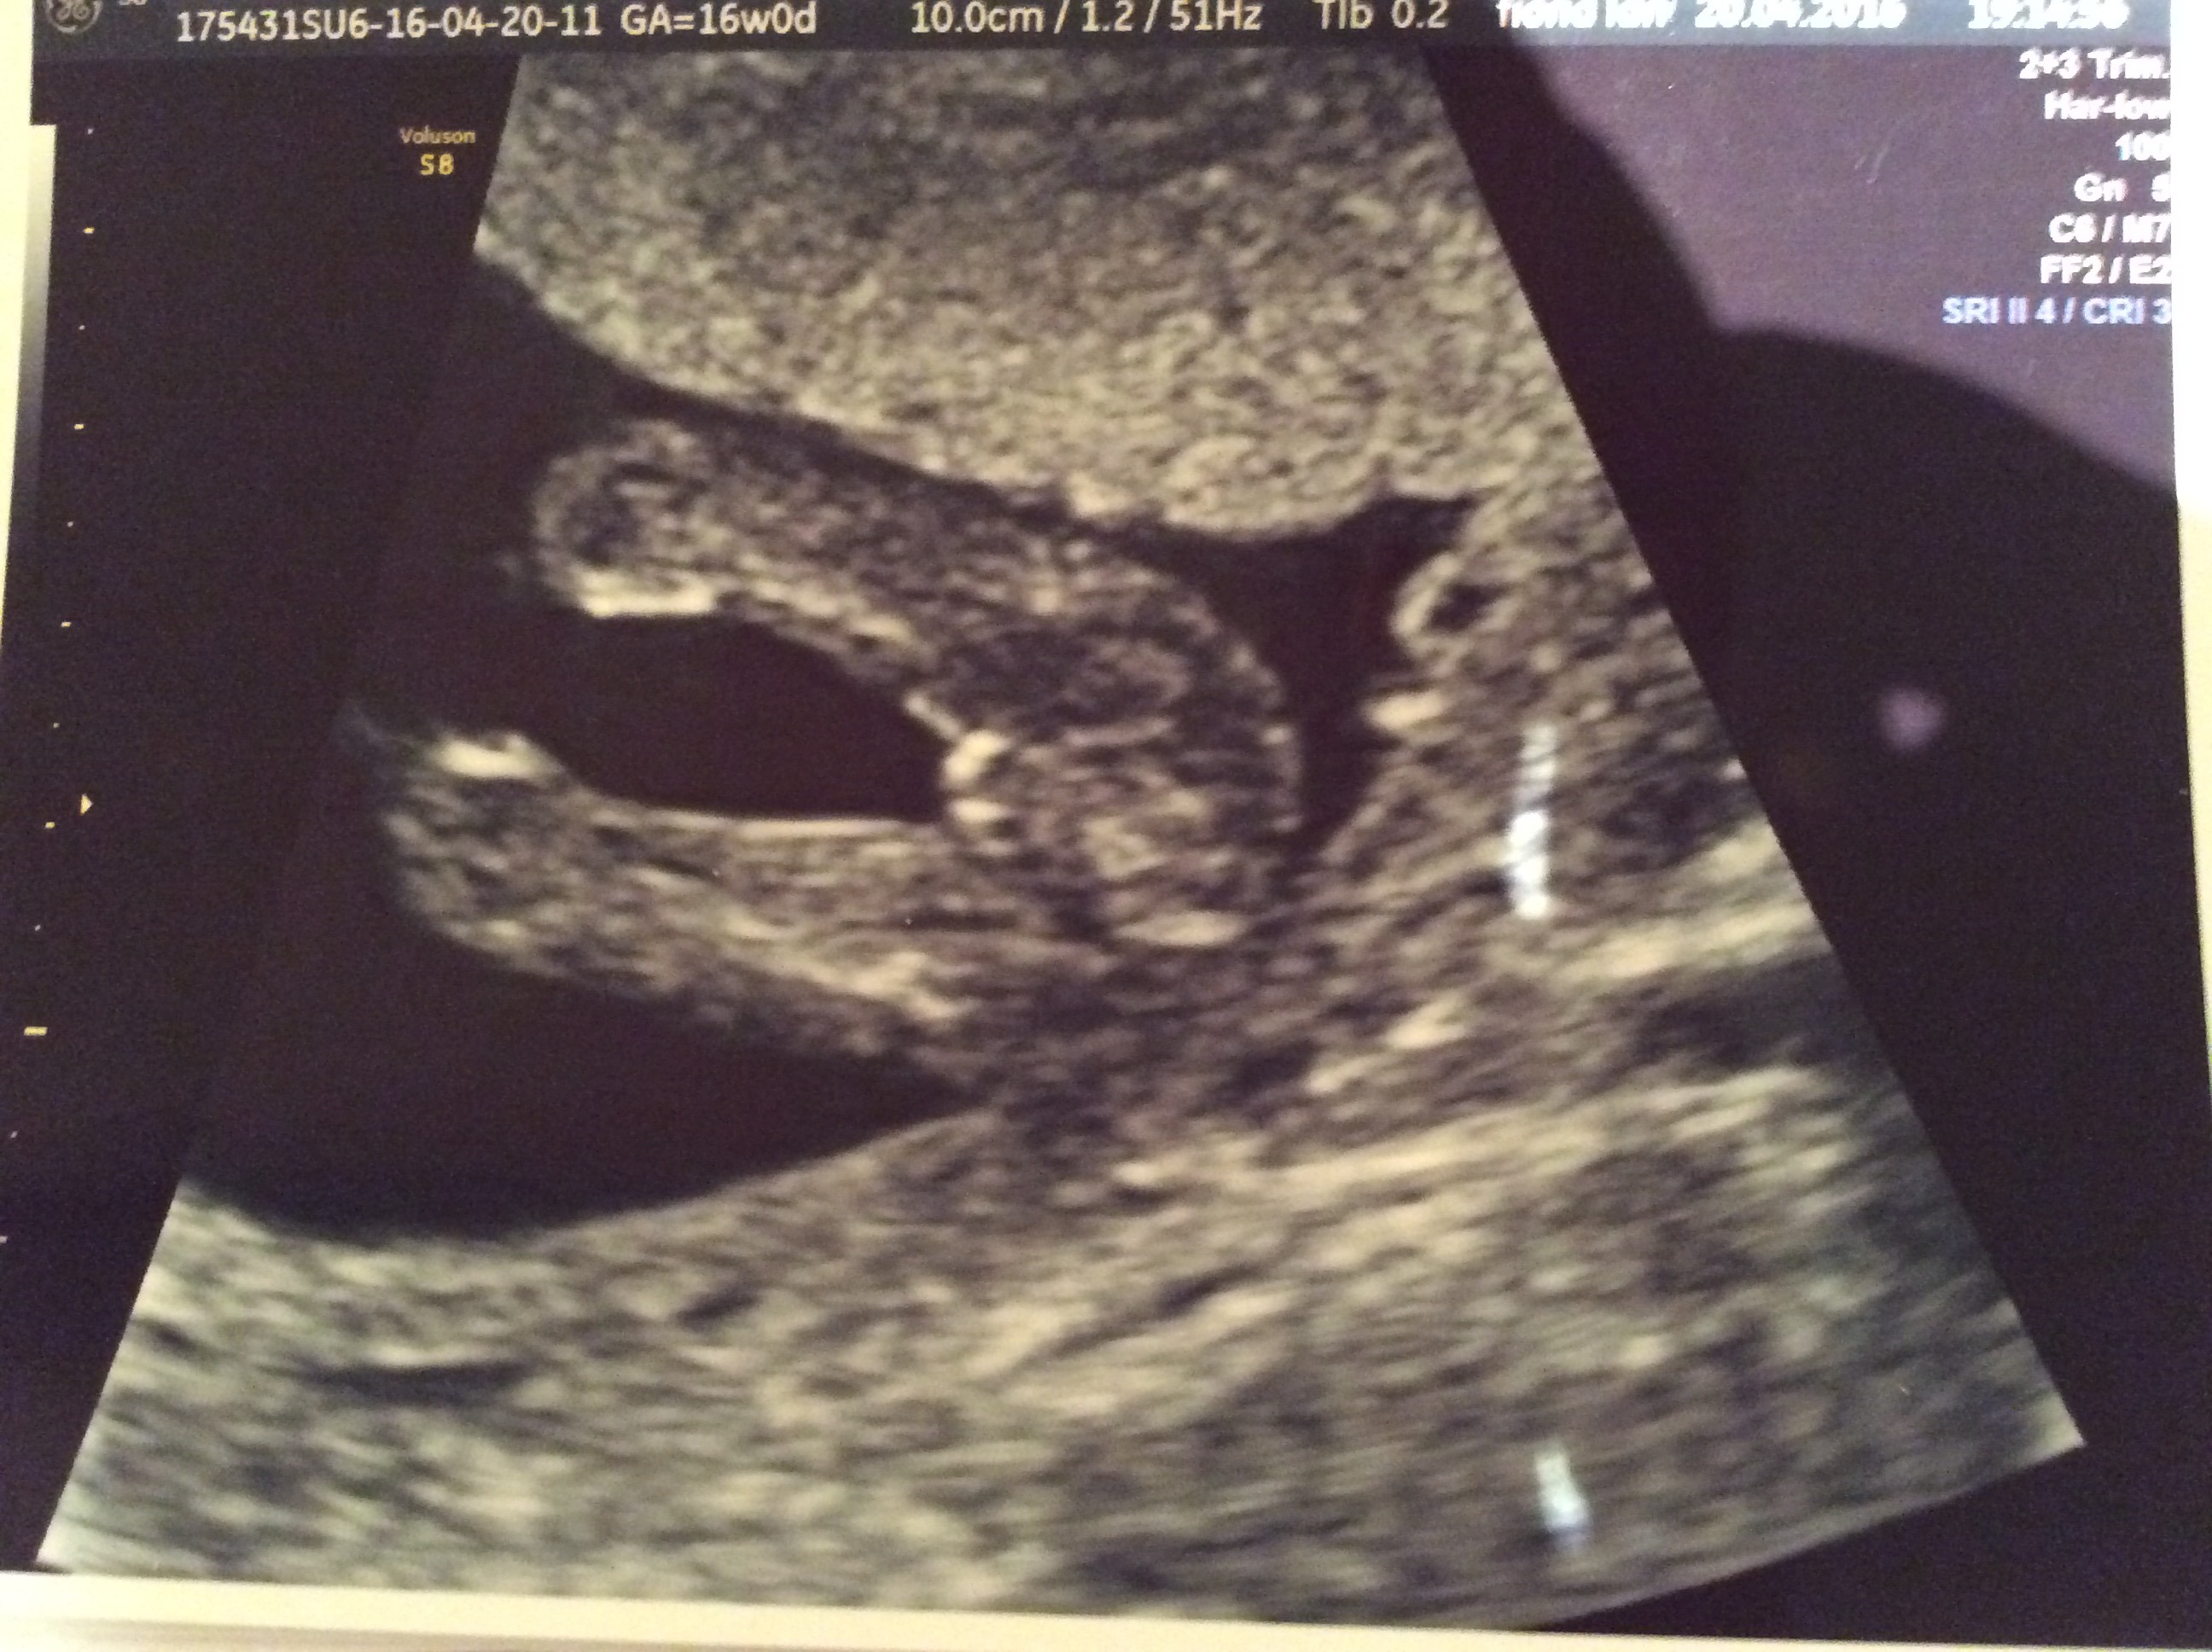

We had a potty shot done at a scan yesterday but my husband asked that they didn't tell us the baby's sex. I am useless at this but I think this looks girly I would love it if you guys could tell me for sure??